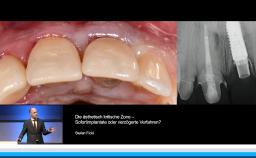

- die Wahl des idealen Implantationszeitpunktes in der ästhetisch kritischen Zone verstehen

- die GBR als Technik zur verzögerten Sofortimplantation in der Praxis anwenden können